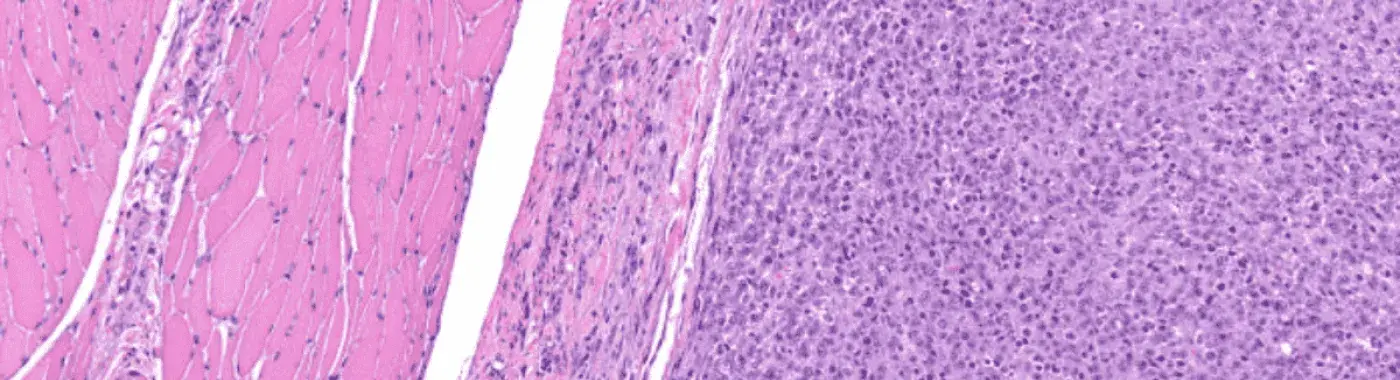

Rhabdomyosarcoma is a type of cancer that occurs in soft tissues. These cancers are one of the rarest forms and affect the skeletal tissues or sometimes hollow organs like the uterus and bladder. It is common in children, but the disorder can affect people at any age.

The name rhabdomyosarcoma derives from the term rhabdomyoblasts, which are the cells from which this cancer arises. When the human embryo is only a few weeks old, these cells begin to develop. They eventually transform into tissues that make up the skeletal muscles, which are the muscles that facilitate the body’s movement.

1. Embryonal Rhabdomyosarcomas are the most common types among such cancers. Children younger than five years are usually affected by this disorder.. ERMS tends to occur in the bladder, vagina, or head and neck area, or in or around the prostate and testicles.

2. Alveolar Rhabdomyosarcomas tend to grow faster and spread more rapidly too. They can occur in older age groups and affect larger muscles of the trunk, arms, and legs.

3. Anaplastic Rhabdomyosarcomas are rare in children.